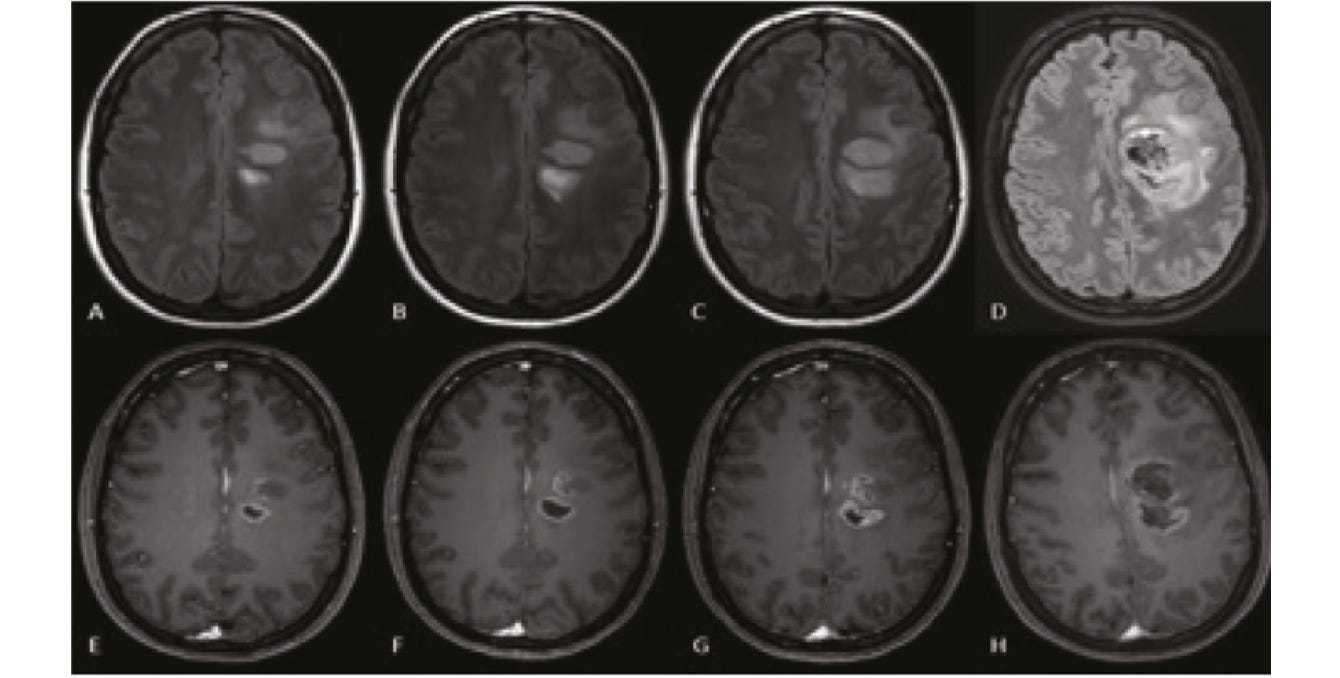

💉 The newly published (January 3rd), peer-reviewed study in Oncotarget does something that was functionally forbidden for four years: it systematically catalogs cancer cases temporally associated with covid vaccination and covid infection, then asks —carefully, explicitly— whether mRNA might plausibly connect the dots.

The second, and perhaps bigger reason, is that the two researchers didn’t conduct a new experiment that could be sliced and diced by Big Pharma’s stable of pet critics. Instead, they reviewed 69 other peer-reviewed publications from 27 different countries, covering 333 patients, plus several large population-level datasets, and proved recurring patterns that simply cannot be waved away:

unusually rapid cancer progression,

reactivation of previously controlled disease,

odd tumor clusters near injection sites or draining lymph nodes, and

a striking overrepresentation of lymphomas, leukemias, aggressive solid tumors, and virus-associated cancers.

Even as they were cautious about identifying a biological mechanism of injury or making direct claims about causality, they painstakingly catalogued a Devil’s inventory of case reports (and a few small series studies) of cancers linked to jabs— including lymphomas, leukemia, sarcoma, carcinoma (pancreatic, prostate, lung, colon, breast, etc.), melanoma (eye and skin cancer), glioblastoma (brain cancer), and the catchall, other.